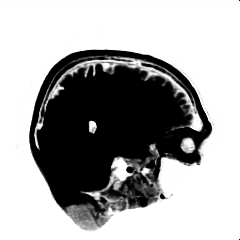

We introduce a neural network framework, utilizing adversarial learning to partition an image into two cuts, with one cut falling into a reference distribution provided by the user. This concept tackles the task of unsupervised anomaly segmentation, which has attracted increasing attention in recent years due to their broad applications in tasks with unlabelled data. This Adversarial-based Selective Cutting network (ASC-Net) bridges the two domains of cluster-based deep learning methods and adversarial-based anomaly/novelty detection algorithms. We evaluate this unsupervised learning model on BraTS brain tumor segmentation, LiTS liver lesion segmentation, and MS-SEG2015 segmentation tasks. Compared to existing methods like the AnoGAN family, our model demonstrates tremendous performance gains in unsupervised anomaly segmentation tasks. Although there is still room to further improve performance compared to supervised learning algorithms, the promising experimental results shed light on building an unsupervised learning algorithm using user-defined knowledge.